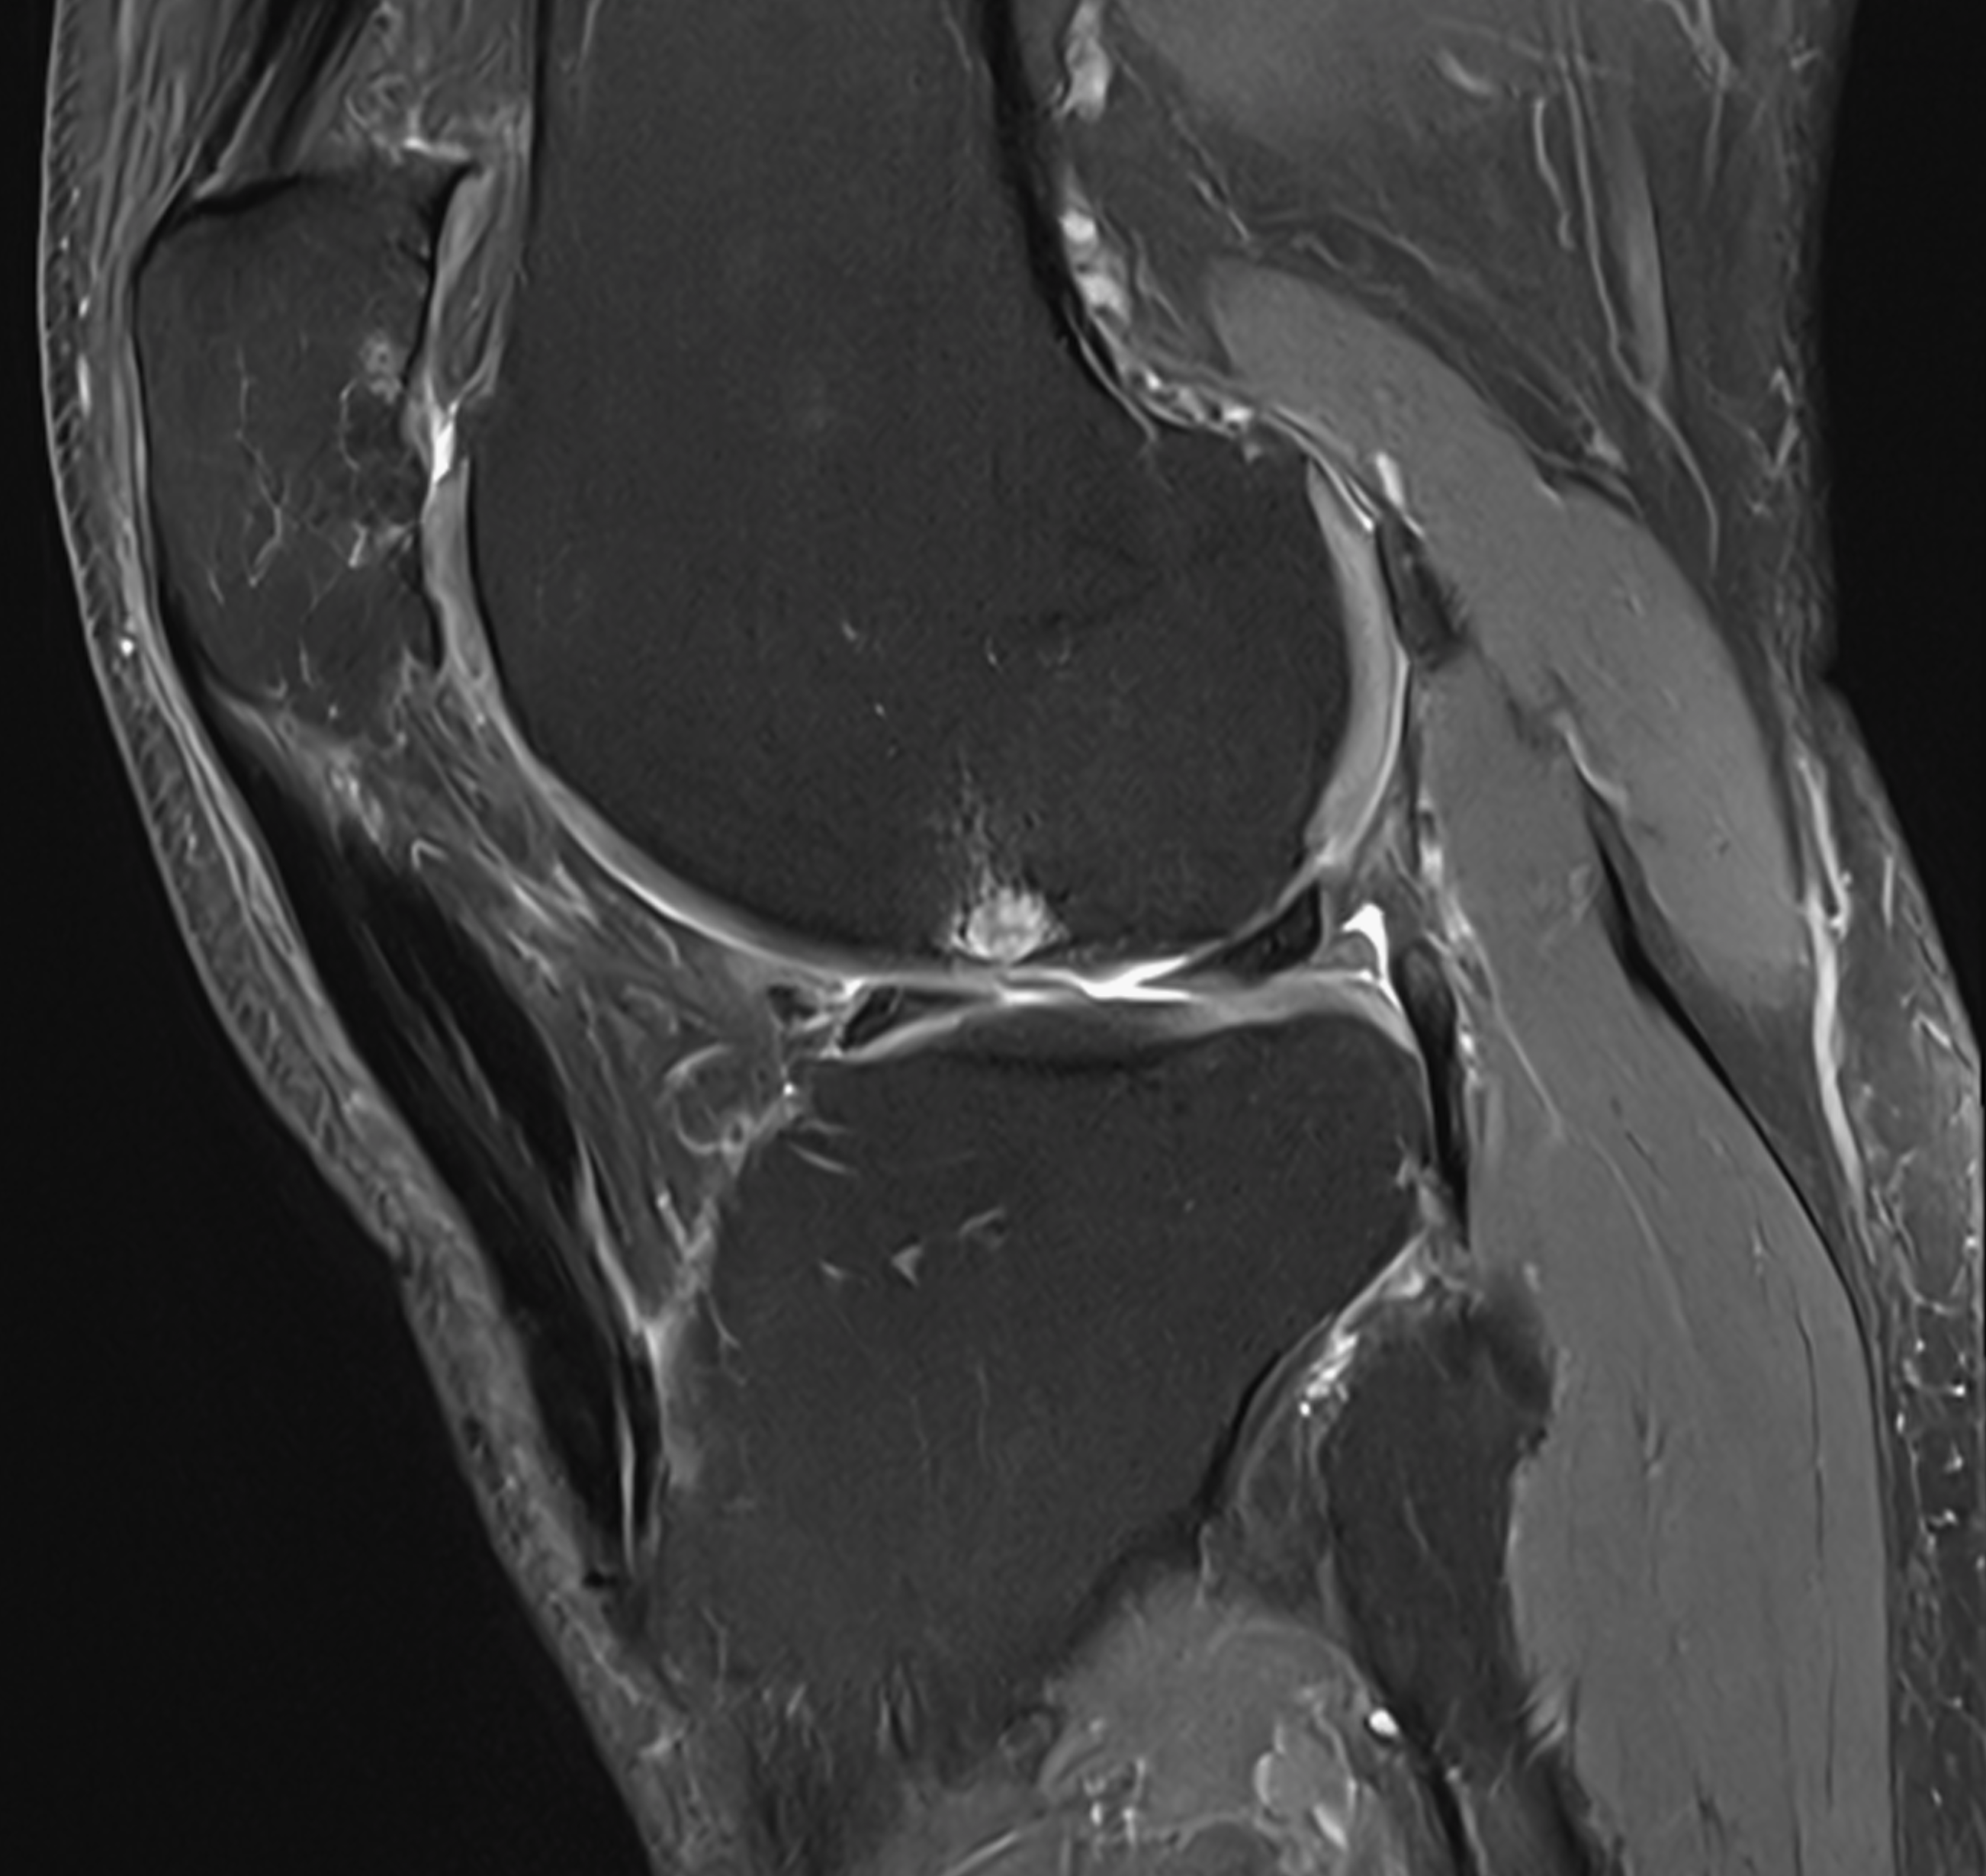

3. Double crossed patellar tendon